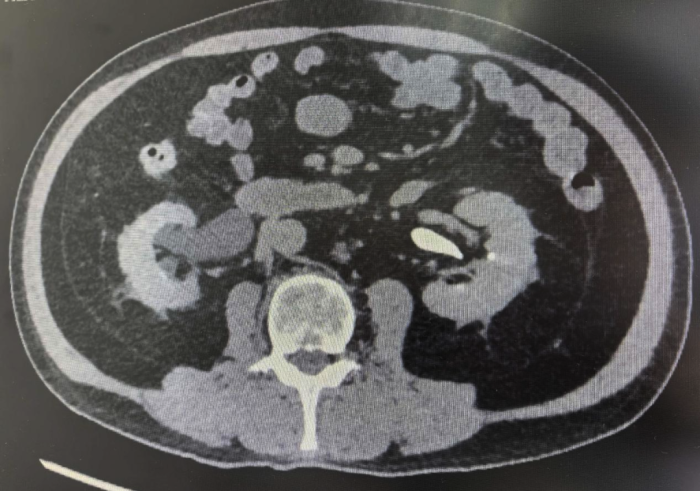

其中,来自湖南的钟先生(化名)一个月前在例行体检中发现右肾存在占位性病变,后经进一步检查确诊为右肾肿瘤,亟须手术干预。出于对桂林医院品牌技术的高度信任,他专程从外地赶来,希望寻求一种既能切除肾脏肿瘤又能保留肾脏功能的治疗方案。

在各项准备工作就绪的情况下,赵洪青教授带领泌尿外科团队,借助达芬奇机器人手术系统卓越的微创与精准优势,为两名患者实施了达芬奇机器人辅助下腹腔镜肾癌根治术。手术过程非常顺利,肿瘤被完整切除。这不仅实现了出血量少、切除彻底的目标,更重要的是最大限度地保留了正常的肾组织,将对肾功能的影响降到了最低。